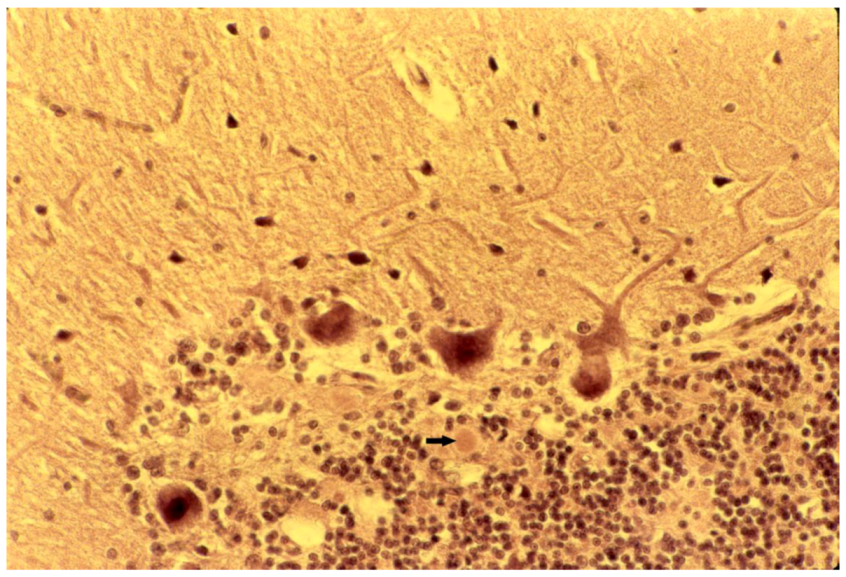

8. Neuropathology

- Klatzo, I.; Gajusek, D.C.; Zigas, V. Evaluation of Pathological Findings in Twelve Cases of Kuru. In Encephalitides; van Boagert, L., Radermecker, J., Hozay, J., Lowenthal, A., Eds.; Elsevier Publ. Comp.: Amsterdam, The Netherlands, 1959; pp. 172–190. [Google Scholar]

- Klatzo, I.; Gajusek, D.C. Pathology of kuru. Lab. Invest. 1959, 8, 799–847. [Google Scholar]

- Fowler, M.; Robertson, E.G. Observations on kuru. III: Pathological features in five cases. Australas Ann. Med. 1959, 8, 16–26. [Google Scholar]

- Kakulas, B.A.; Lecours, A.-R.; Gajdusek, D.C. Further observations on the pathology of kuru. J. Neuropathol. Exp. Neurol. 1967, 26, 85–97. [Google Scholar] [CrossRef]

- Neuman, M.A.; Gajdusek, D.C.; Zigas, V. Neuropathologic findings in exotic neurologic disorder among natives of the Highlands of New Guinea. J. Neuropathol. Exp. Neurol. 1964, 23, 486–507. [Google Scholar] [CrossRef]

- Liberski, P.P.; Sikorska, B.; Lindenbaum, S.; Goldfarb, L.G.; McLean, C.; Hainfellner, J.A.; Brown, P. Kuru: Genes, cannibals and neuropathology. J. Neuropathol. Exp. Neurol. 2012, 71, 92–103. [Google Scholar] [CrossRef]

- Hainfellner, J.; Liberski, P.P.; Guiroy, D.C.; Cervénaková, L.; Brown, P.; Gajdusek , D.C.; Budka, H. Pathology and immunohistochemistry of a kuru brain. Brain Pathol. 1997, 7, 547–554. [Google Scholar] [CrossRef]

- McLean, C.A. The neuropathology of kuru and variant Creutzfeldt-Jakob disease. Phil. Trans. R. Soc. 2008, 363, 3685–3687. [Google Scholar] [CrossRef]